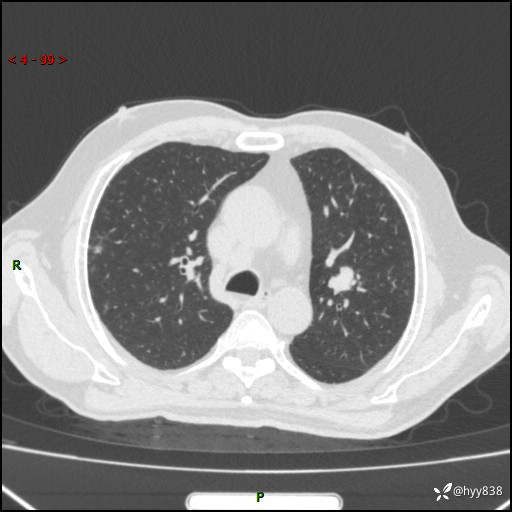

简要病史:患者4月前无明显诱因后背正中间疼痛,间断阵痛,无低热、咳嗽,盗汗、咯血、胸痛、喘气等不适,2024-2-25当地第二人民医院胸部CT提示“1.双肺感染病变;2.左肺上叶及右肺中叶结节灶;3.双肺肺气肿并肺大泡4.纵膈淋巴结肿大5.主动脉及冠脉硬化,今为求明显结节性质遂来我院门诊就诊,门诊以“肺占位”收治入院。 起病以来,患者精神饮食睡眠一般,大小便正常,体力体重无明细变化。

辅助检查:CT

临床诊断:肺占位

增强